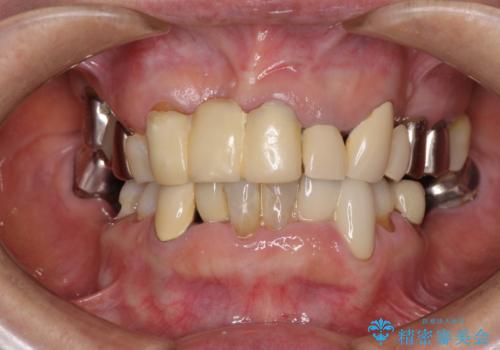

着色が著しい前歯のブリッジをオールセラミックできれいに

- 保険診療の前歯のブリッジが、形態も色も不自然で気になるとのことで来院された患者様です。

神経の抜かれている土台の歯は根管治療を行った上で、オールセラミックブリッジにより補綴することとしました。